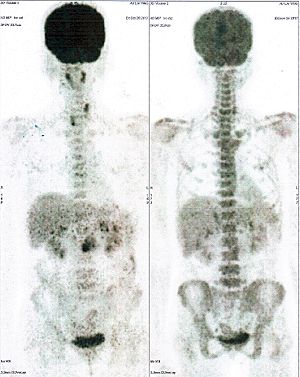

CASE NO: 5 (BREAST CANCER)

A middle-aged woman with breast cancer that has spread to the anterior chest wall, and numerous chemotherapy could not stop the spread of cancer. After a few treatment, almost all the cancer went into remission. About 6 months later, she is still in remission.

CASE NO: 6 (BREAST CANCER)

A middle-aged women treated for breast cancer now presents with massive liver metastases and a few bone metastases. She refused conventional chemotherapy and came to see us. After just 2 treatment, most of the cancer went into remission and those remaining are less active. Treatment will continue until complete remission.